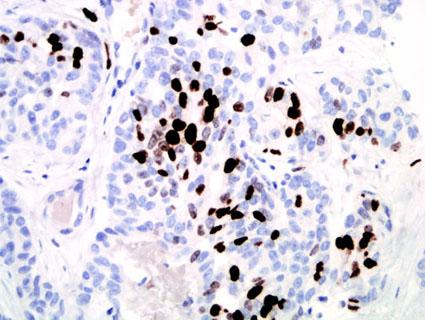

Proliferation index is an important prognostic factor in breast cancer. The Ki-67 protein is expressed in all phases of the cell cycle except G0 and serves as a good marker for proliferation. Studies that have evaluated proliferation index by Ki-67 IHC in breast cancer have shown a significant correlation between high proliferation rates and shorter disease free and overall survival(1-4).

The Ki-67 proliferation index is assessed by point counting 500 to 1000 cells and is reported as percent positive cells. The cut-off to define a high Ki-67 proliferation index is not well-established or universally agreed upon. In our laboratory, we use 20 percent positive cells to define "positive" (i.e. high risk) based on the results of studies we feel are currently the best available in the medical literature (1, 2). See detailed staining procedure.